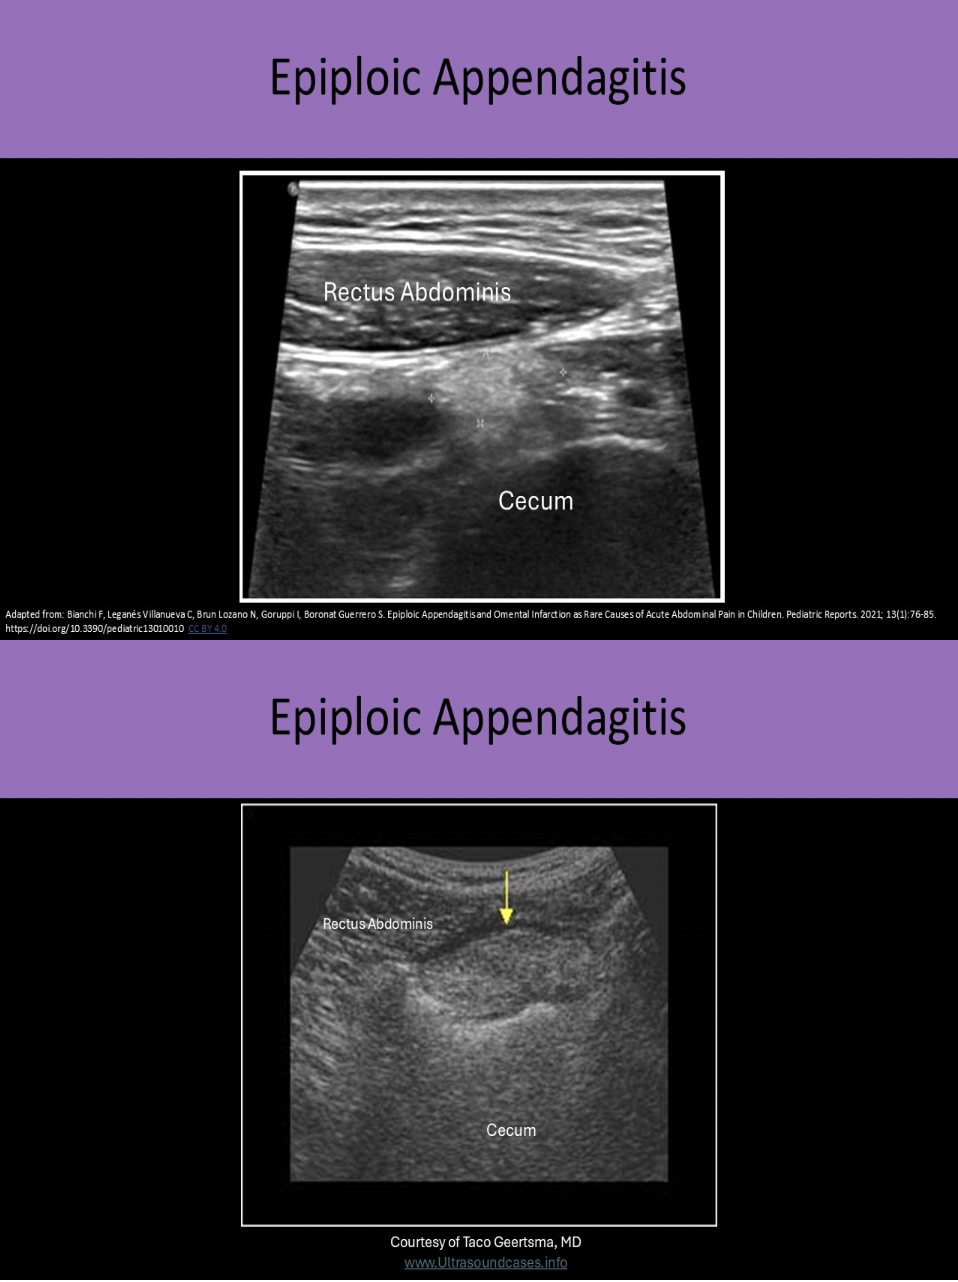

What is a epiploic appendagitis?

D. inflammation of the thick fatty strands that attach to the serosal surface of the colon

Epiploic appendages are thick fatty strands that attach to the serosal surface of the colon. Torsion or thrombosis of these strands can cause ischemia or infarction. This leads to localized inflammation and pain. On US it appears as an echogenic finger-like projection from the colon wall. The surrounding pericolic fat becomes thickened and echogenic. It can simulate appendicitis and it is very important to differentiate the two because the treatments are very different.